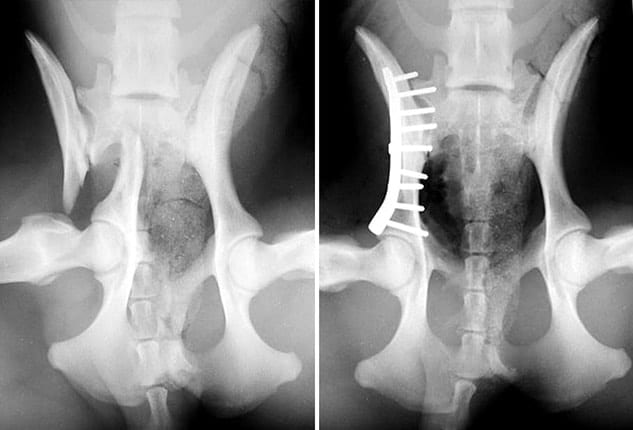

Plats and screws

Plate and screws are an advanced surgical procedure that is used for severe fractures in pets. Bone plates and screws are one of the most developed and stable fracture restoration techniques available in veterinary medicine. A steel plate is attached to the exterior of the bone using screws. This holds the damaged portions firmly in vicinity, allowing them to heal correctly.

- Used for the severe and highly complex fractures

- Its advantage is that it is very strong and fixes the fractures tightly.

- The risk of healing is not there. Fractured bone heals completely.

- It is an expensive treatment, and it needs proper surgery.

- The recovery time is also prolonged and needs proper check-ups and regular doctor visits.

Plates are used only for the severe cases when the fractured bone is not able to heal properly, or other options cannot be used.